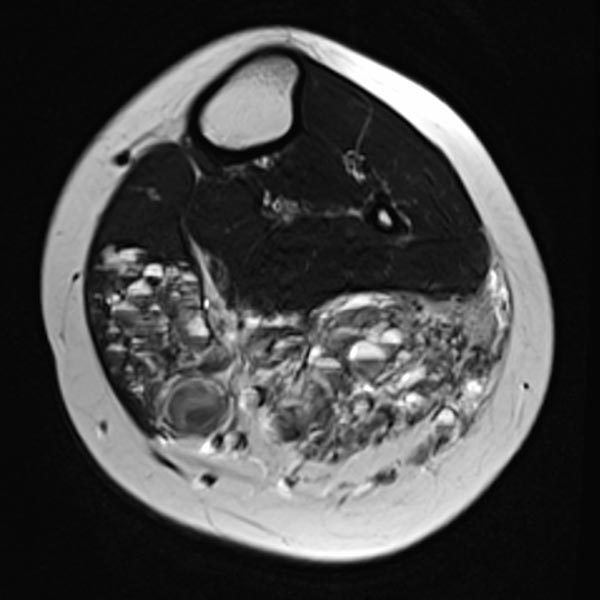

In der axialen T2-gewichteten MRT des linken Unterschenkels finden sich mehrere dilatierte, dysplastische Venen im Sinne einer venösen Malformation in der gesamten oberflächlichen Flexorenmuskulatur. Durch den niedrigen Durchfluss kommt es zur Stase des Blutes innerhalb der Malformation mit der Bildung von Flüssigkeits-Spiegeln. Praktisch der gesamte Muskel ist von Malformation und Fettgewebe durchsetzt. Großer Thrombus in einer dilatierten, dysplastischen Vene.

Auch in der axialen Kontroll-MRT in T2-Wichtung sind die Gefäßkanäle zum großen Teil verschlossen. Nach erfolgreichem Verschluss bleibt aber ein schwarz-weißes „Salz-und-Pfeffer-Muster“ bestehen, das typisch für eine FAVA ist. Es besteht aus Fettgewebe (hyperintens) und Bindegewebe (hypointens).